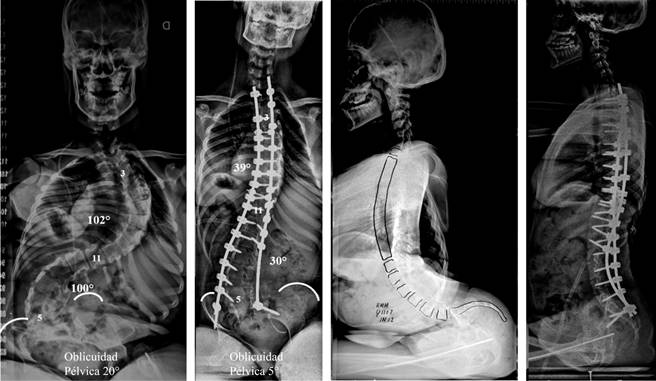

Para el análisis radiográfico se realizaron espinogramas de frente y perfil, sentado o parado según el estatus neurológico del paciente. Se incluyeron: el espinograma prequirúrgico, el postquirúrgico inmediato y el del último control (Figuras 1 y 2). Se utilizó el método de Cobb para la medición de las curvas en el plano coronal y sagital. Los parámetros analizados en plano frontal fueron: magnitud de la curva escoliótica, oblicuidad pélvica (ángulo formado entre la línea tangencial entre ambas espinas ilíacas anterosuperior y la paralela al piso) y balance coronal global (distancia horizontal desde la línea de la plomada del centro del cuerpo de C7 respecto de la línea vertical sacra media).

En el plano sagital se analizó: la cifosis dorsal (desde el platillo cefálico de T3 hasta el platillo caudal de T12) y el balance sagital global (distancia horizontal desde la línea de la plomada desde C7 respecto del ápex posterior de S1). También se evaluó la integridad y posición de los implantes.

a. Curva escoliótica: la magnitud promedio preoperatoria de la curva escoliótica mayor fue de 90o (rango 43-137o). El promedio en el postoperatorio inmediato fue de 39o (rango 5-75o). Corrección promedio de 56%. La deformidad promedio observada en el último control fue de 43o (rango 5-75o). Corrección promedio de 52% con respecto al prequirúrgico.

b. Balance coronal global: la magnitud promedio preoperatoria del balance coronal fue de 28.4 mm (rango 0-76 mm) en el prequirúrgico, de 14.5 mm (rango 0-40 mm) en el postquirúrgico inmediato y de 17 mm (rango 0-44 mm) en el último control. Corrección promedio de 40% con respecto al prequirúrgico.

c. Oblicuidad pélvica: la magnitud promedio prequirúrgica de la oblicuidad pélvica fue de 19o (rango 0-48o) en el prequirúrgico y de 7o (rango 0-23o) en el postquirúrgico inmediato. Corrección promedio de 63%. En el último control la oblicuidad pélvica fue de 9o (rango 0-27o). Corrección promedio de 53% con respecto al prequirúrgico.

a. Cifosis: la magnitud promedio prequirúrgica de la cifosis torácica fue de 50o (rango 5-151o) en el prequirúrgico y de 37o (rango 5-70o) en el postquirúrgico inmediato. Corrección promedio de 26%. En el último control la cifosis fue de 41o (rango 5-75o). Corrección promedio de 18% con respecto al prequirúrgico.

b. Balance sagital: la magnitud promedio preoperatoria del balance sagital fue de 63.3 mm (rango 15-115 mm) en el prequirúrgico, de 30.4 mm (rango 4-114 mm) en el postquirúrgico inmediato y de 38.3 mm (rango 4-160 mm) en el último control. Corrección promedio de 40% con respecto al prequirúrgico.